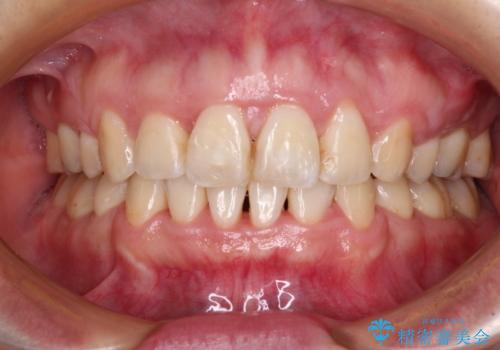

- 出っ歯と口の閉じにくさ、デコボコを気にして来院された患者様です。

口元の突出感を改善するため、上下左右第一小臼歯4本の抜歯を行い、ワイヤー装置による矯正治療を行うこととしました。

上下前歯の距離が大きかったため、上下の歯が接触するまでに時間がかかりました。

それでも目安である2年半で終えることができ、患者様には大変満足していただけました。